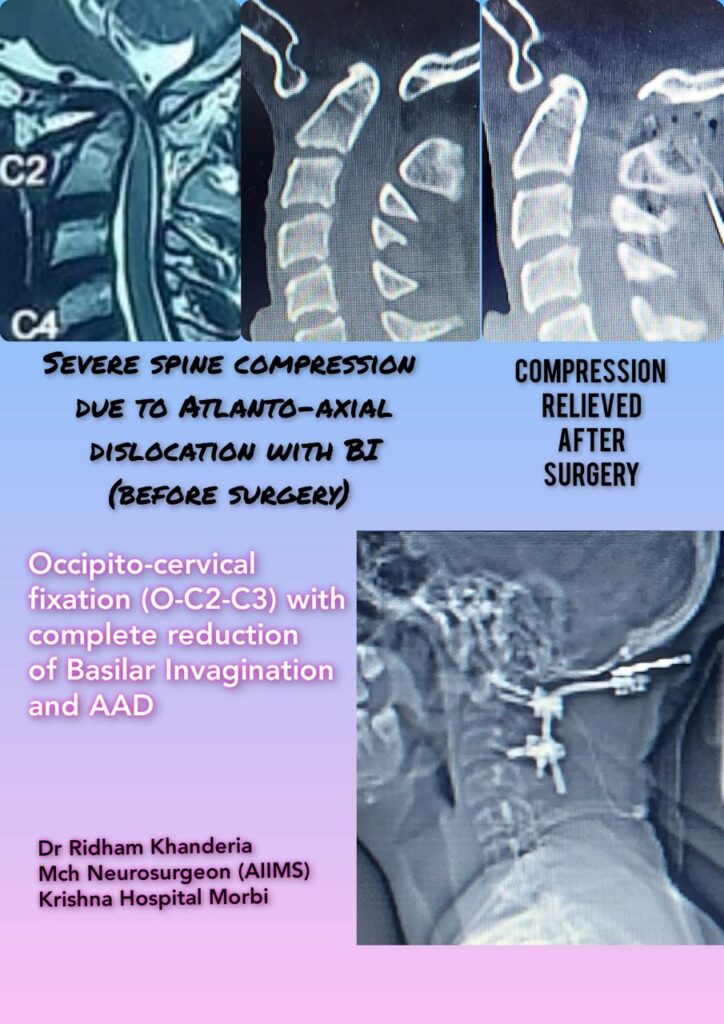

He specializes in back pain, slip disc, sciatica, and complex spine and brain disorders, with a strong focus on conservative treatment, minimally invasive surgery, and ethical, patient-centered care.